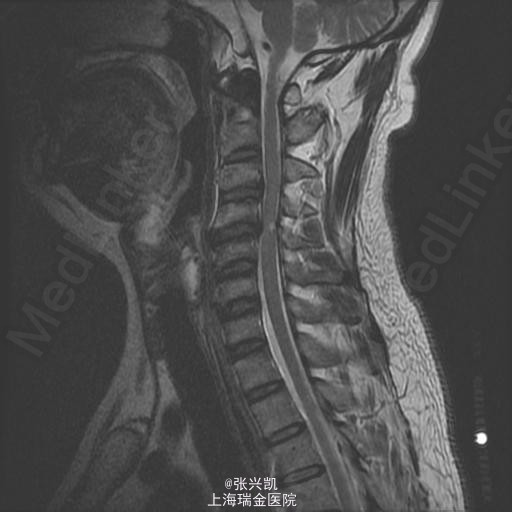

上肢麻木5年,下肢无力3月余 患者男,45 岁 5年前双上肢麻木,伴有下肢无力感,足底脚踩棉花感,近期无力症状加重。曾于外院检查,诊断为“颈椎病”。具体不详,既往体健。

查体: 脊柱无侧弯畸形,上肢运动可,感觉麻木,肌力可,肱二,三头肌肌腱反射(+),双足肿胀,双侧髂腰肌肌力可,股四头肌肌张力亢进,跟膝腱反射亢进。足底感觉异常。 检查:MRI :C3-4,4-5椎间盘突出伴椎管狭窄,C4-5见脊髓变性改变

诊断:C3-4,C4-5椎间盘突出伴椎管狭窄 处理: 颈椎前路减压融合内固定术